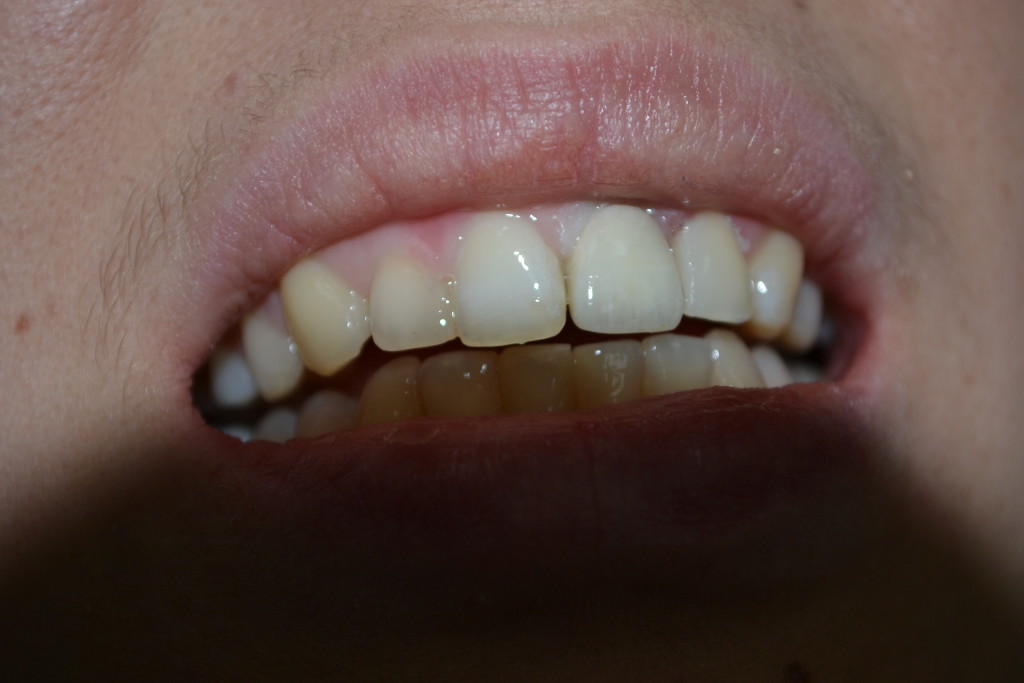

- результаты протезирования